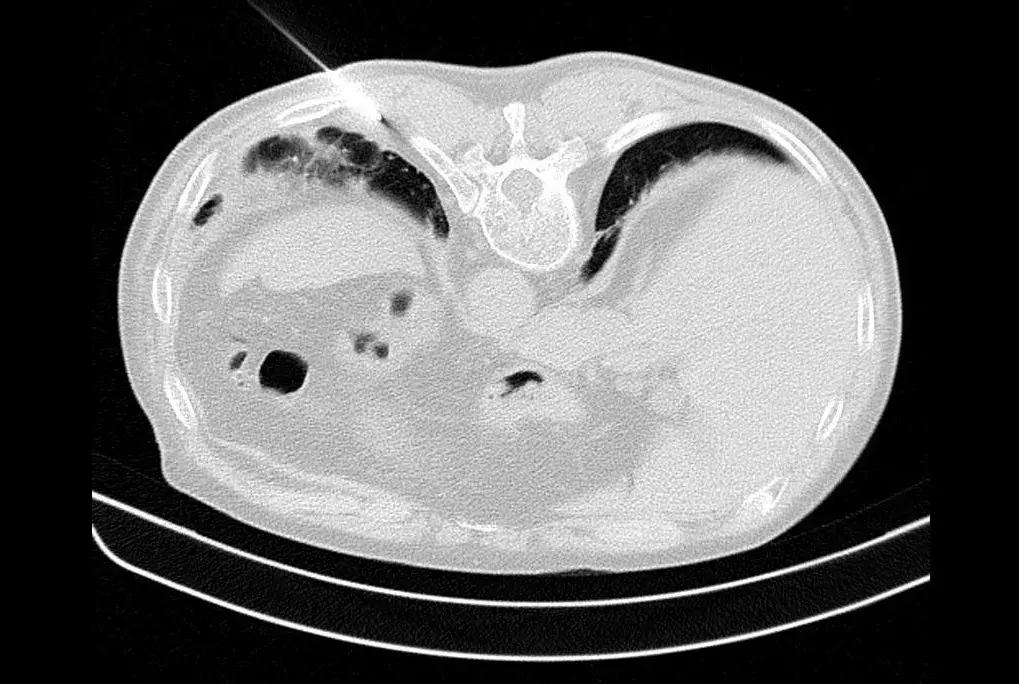

仔细阅读CT,识别胸膜增厚点是成功的第一步

我们可以看到CT图像上,选择胸膜较厚的地方来进行穿刺,阳性率较高,反之阳性率较低(箭头为增厚部位)。

如下图,选择增厚、病变比较明显的地方进行穿刺,阳性率较高。